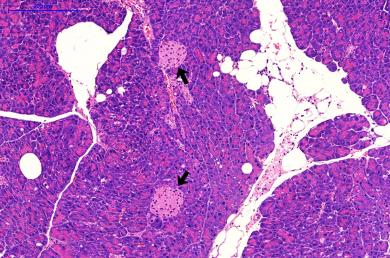

► Adipocytes (white) and islets of Langerhans (black arrows) in the pancreas of a diabetes-prone New Zealand Obese (NZO) mouse. Light microscope image, scale 200 micrometer, hematoxylin-eosin staining (photo: DIfE)

Fatty liver has been thoroughly investigated as a known and frequently occurring disease. However, little is known about excess weight-induced fat accumulation in the pancreas and its effects on the onset of type 2 diabetes. The research team led by Professor Annette Schürmann and Professor Tim J. Schulz of the German Institute of Human Nutrition (DIfE) has now found that overweight mice prone to diabetes have a high accumulation of fat cells in the pancreas. Mice resistant to diabetes due to their genetic make-up despite excess weight had hardly any fat in the pancreas, but instead had fat deposits in the liver. "Fat accumulations outside the fat tissue, e.g. in the liver, muscles or even bones, have a negative effect on these organs and the entire body. What impact fat cells have within the pancreas has not been clear until now," said Schürmann, head of the Department of Experimental Diabetology at DIfE and speaker of the German Center for Diabetes Research (DZD).

In order to find out how fat cells might impair the function of the pancreas, researchers led by Schürmann and Schulz isolated adipocyte precursor cells from the pancreas of mice for the first time and allowed them to differentiate into mature fat cells. If the mature fat cells were subsequently cultivated together with the Langerhans islets** of the pancreas, the beta cells of the "islets" increasingly secreted insulin. "We suspect that the increased secretion of insulin causes the Langerhans islets of diabetes-prone animals to deplete more quickly and, after some time, to cease functioning completely. In this way, fat accumulation in the pancreas could contribute to the development of type 2 diabetes," said Schürmann.

** The islets of Langerhans – also referred to as islet cells or Langerhans islets – are islet-like accumulations of hormone-producing cells in the pancreas. A healthy adult has about one million Langerhans islets. Each "islet" has a diameter of 0.2-0.5 millimeters. The beta cells produce the blood glucose-lowering hormone insulin and make up about 65 to 80 percent of the islet cells. When blood glucose levels are elevated, these secrete insulin into the bloodstream so that the levels are normalized again.